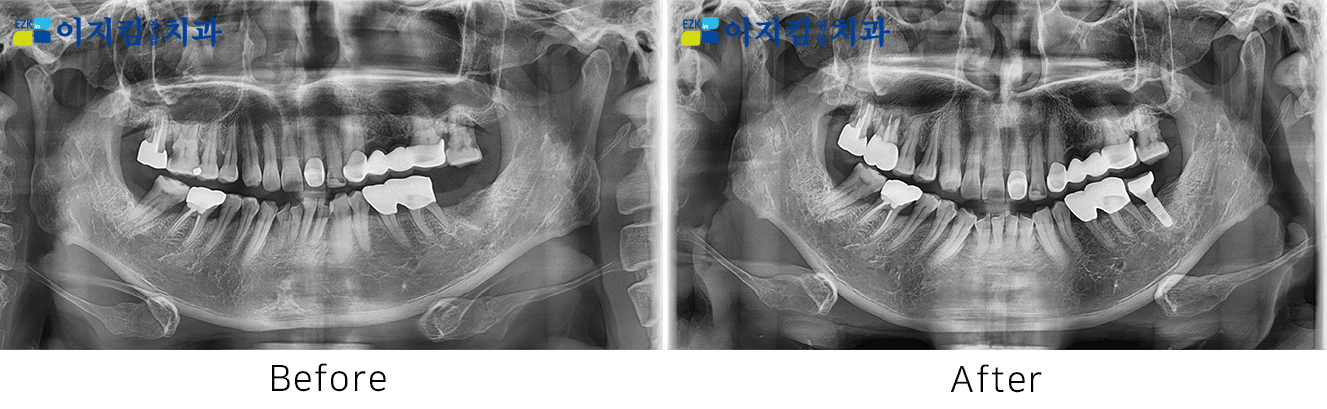

ÀÓÇöõÆ® Àü ¡¤ ÈÄ »çÁø

[

Á¶È¸¼ö : 2908

]